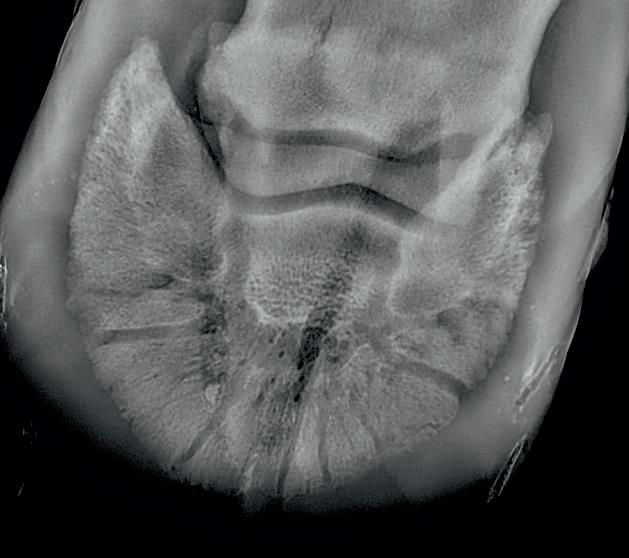

Radiographic proof in clinical results

BONE Gold nutritional bone joint and collagen supplement was formulated to provide some of the essential amino acid requirements of collagen type I, II and III (found in bone and connective tissue) in addition to supporting the nitric oxide pathway which has been found to assist in the formation of bone callus postinjury.

Veterinary surgeons have recommended that Bone Gold may assist with sore shins, tendon injuries, ligament injuries, osteoarthritis and post-surgery in horses and polyarthritis, geriatric osteoarthritis, and post-surgery in dogs.

Here is a veterinary radiographic report on a horse with a fracture evident on the medial toe and after treatment and feeding Bone Gold during this period. More information on these products can be found at www.vetgold.com.au

VETERINARY RADIOGRAPHIC REPORT

HORSE: "XXXXXXXX"

DATES OF EXAMINATION: 26TH AUG, 21ST OCT 21 & 17TH NOV '21

PLACE: XXXXXXXXXX FARM

XXXXXXX's left and right front feet were radiographed on 26th Aug, 21st Oct (8 weeks) and again on the 17th Nov '21(12 weeks).

RADIOGRAPHS:

26.08.21: Right Front: Large P3 solar margin fracture evident on medial toe 32.6mm x 4.1mm with approximately 1.4mm separation from parent bone as below left image.

21.10.21: Right Front: Fine residual 4.2mm fracture still evident, approximately 90% resolution

17.11.21: Right Front: Fracture fully resolved

RECOMMENDATIONS:

Radiographic results as of the 17th Nov '21 show total resolution of the original fracture.

XXXXXXX was reshod today utilising off an alloy shoe with a toe clip - inner circumference seated out to avoid any sole pressure.

The horse can return to training. Please do not hesitate to contact me if you have any further queries

COMMENTS:

Solar margin Type IV fractures of this magnitude have well-documented internationally published healing rates of 7 - 12 months. Full resolution of these fractures is rare as most often the fracture fragments are resorbed.

Full resolution in a 3 month period was not anticipated.

The horse was on Bone Gold 3 x scoops fed once per day for this period.